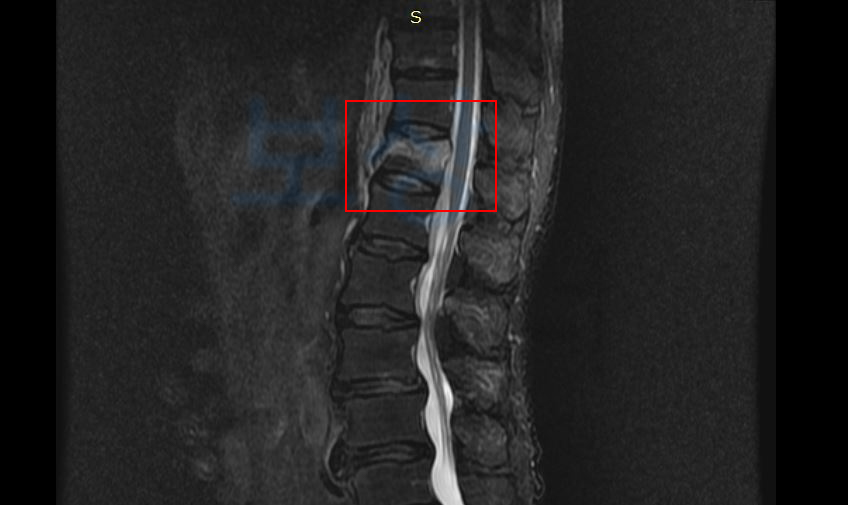

저희 상주하는 노무직원은 영상 CD를 보며 산재장해에 해당하는지 면밀한 검토를 진행했고 그 결과 산재 장해등급 12급 인정받아 장해급여 16,863,000원 지급받으셨습니다.

산재에서는 주치의의 장해 소견서 보험사에서는 의료 전문의의 AMA 방식의 후유 장해 진단서가 필요한데요, 보상 파트너는 공신력 있는 타 병원의 전문의를 통해 후유 장해 진단서를 발급받았고 이를 기초로 손해사정서를 작성하여 보험사에 청구하였습니다.

척추의 중도의 기형 4급,

뚜렷한 기형을 남긴 때 30%!!